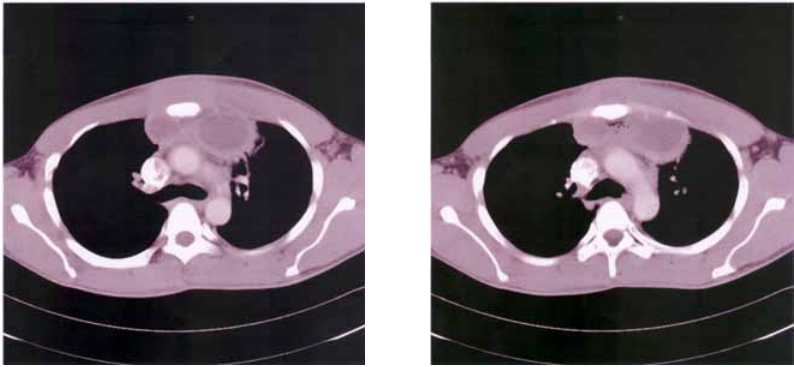

79 35 歲男性,有藥癮病史且 HIV 陽性,主訴胸痛和發燒,CT 如圖示,最正確的診斷應為:

(A)胸腺瘤(thymoma) (B)胸腺囊腫(thymic cyst) (C)肺癌(lung cancer) (D)縱膈腔膿瘍(mediastinal abscess)